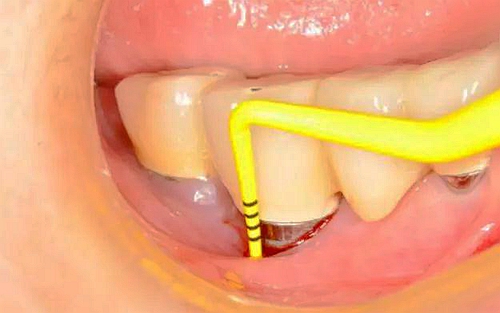

(1)去除病因:有菌斑、牙石沉積的種植體,周同黏膜探診出血陽性,無溢膿,探診深度≤4mm,應(yīng)進行機械除菌斑治療。必須用塑料器械或與種植體同樣硬度的鈦刮治器。

(2)氯已定的應(yīng)用:在探診出血陽性,探診深度4~5mm,有或無溢膿的種植體部位,除機械治療外,還應(yīng)使用氯已定治療。